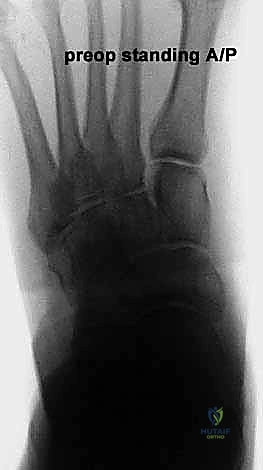

إطالة العمود الجانبي للقدم، أو قطع عظم إيفانز، هو إجراء جراحي حيوي لتصحيح تشوه القدم المسطحة المكتسبة الناتج عن قصور الوتر الظنبوبي الخلفي. يهدف إلى استعادة قوس القدم وتخفيف الألم وتحسين وظيفة القدم، ويتم على يد خبراء مثل الأستاذ الدكتور محمد هطيف.

* الأشعة السينية (X-rays) مع تحمل الوزن: ضرورية لتقييم درجة انهيار القوس وزوايا العظام (مثل زاوية تالونافيكولار Meary's Angle).

* الرنين المغناطيسي (MRI): يُستخدم لتقييم الأنسجة الرخوة، وتحديداً درجة التمزق في الوتر الظنبوبي الخلفي والأربطة الداعمة.